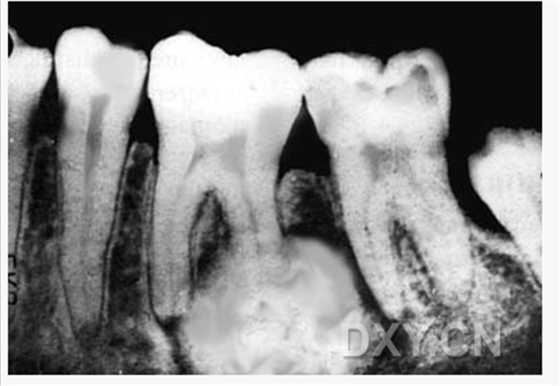

成釉細胞瘤